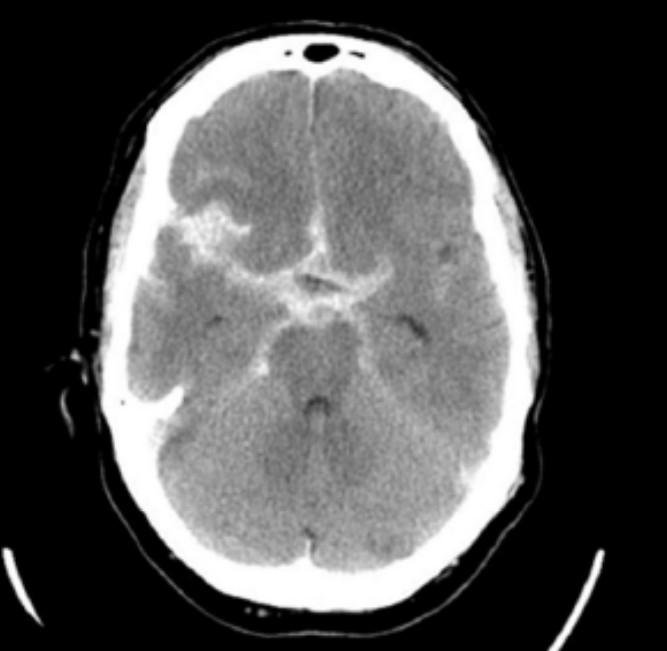

The patient undergoes an urgent CTB.

2. List two CT brain findings on the single non-contrast image. 2 marks

Question image